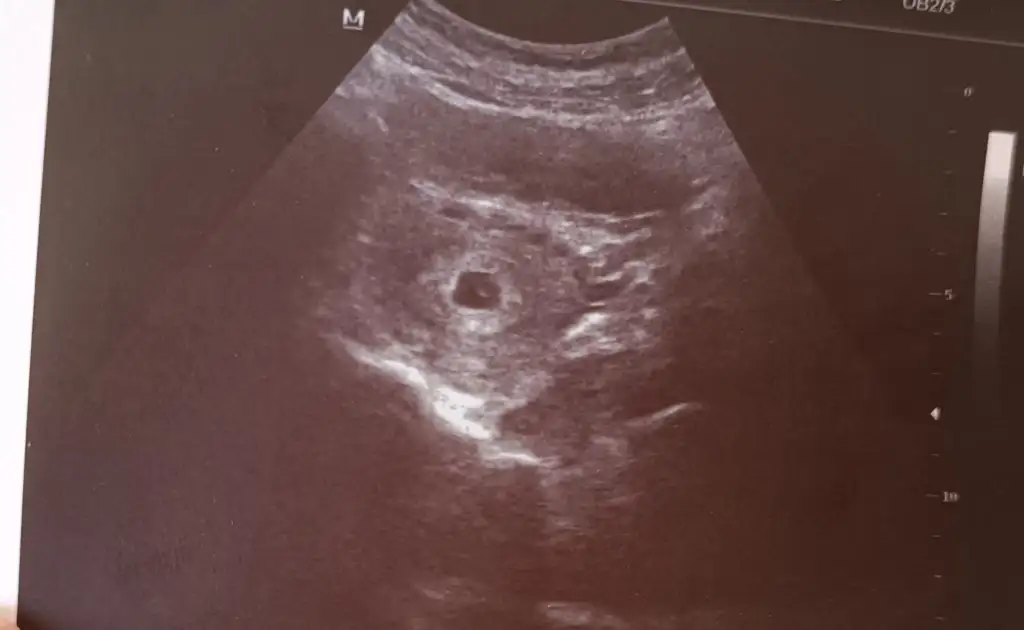

Ölçüm yaptığı şeyKızlar merhaba. Kesede görünen iki beyaz bokta ile ilgili bilgisi olan var mı ?

Eki Görüntüle 3230880

bu haftalarda gördüğüm keselerde tek beyaz nokta görüyorum genelde.

nedir acaba bu beyazlık. ya da anlam ifade etmiyor mu

Teşekkür ederim hiç birsey soylemedi yolk kesesiyle ilgili valla bende gördüm merak ettim bak simdiMaşallahben içinde yolk kesesini de gördüm sanki, yanlış mı görüyorum

Benim ki de öyle çünkü ondan yolk dedimTeşekkür ederim hiç birsey soylemedi yolk kesesiyle ilgili valla bende gördüm merak ettim bak simdi

Seninkinin içindeki o küçük şey yolk kesesimiymis doktor mu söyledi bana niye bisey demedi ki yaBenim ki de öyle çünkü ondan yolk dedim

Bende bugün ilk defa kese gördüm yolk çok belli belirsizdi. Kaç haftalık şuan kesenizin büyüklüğü ne?Benim ki de öyle çünkü ondan yolk dedim